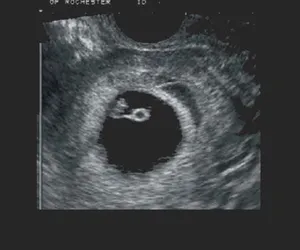

Hamilelikte 3. Hafta

3. haftada fetüs gelişmeye devam eder. Hücre topu çevresinde amniyotik keseye dönüşmüştür ve amniyotik sıvı biriktirmeye başlar ve fetüsün etrafını korumaya alır.